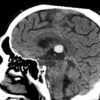

Nang keo não thất

Nang keo não thất - Ảnh 3

» Thông tin: Nữ giới – 70 tuổi.

» Lâm sàng: Đau đầu.